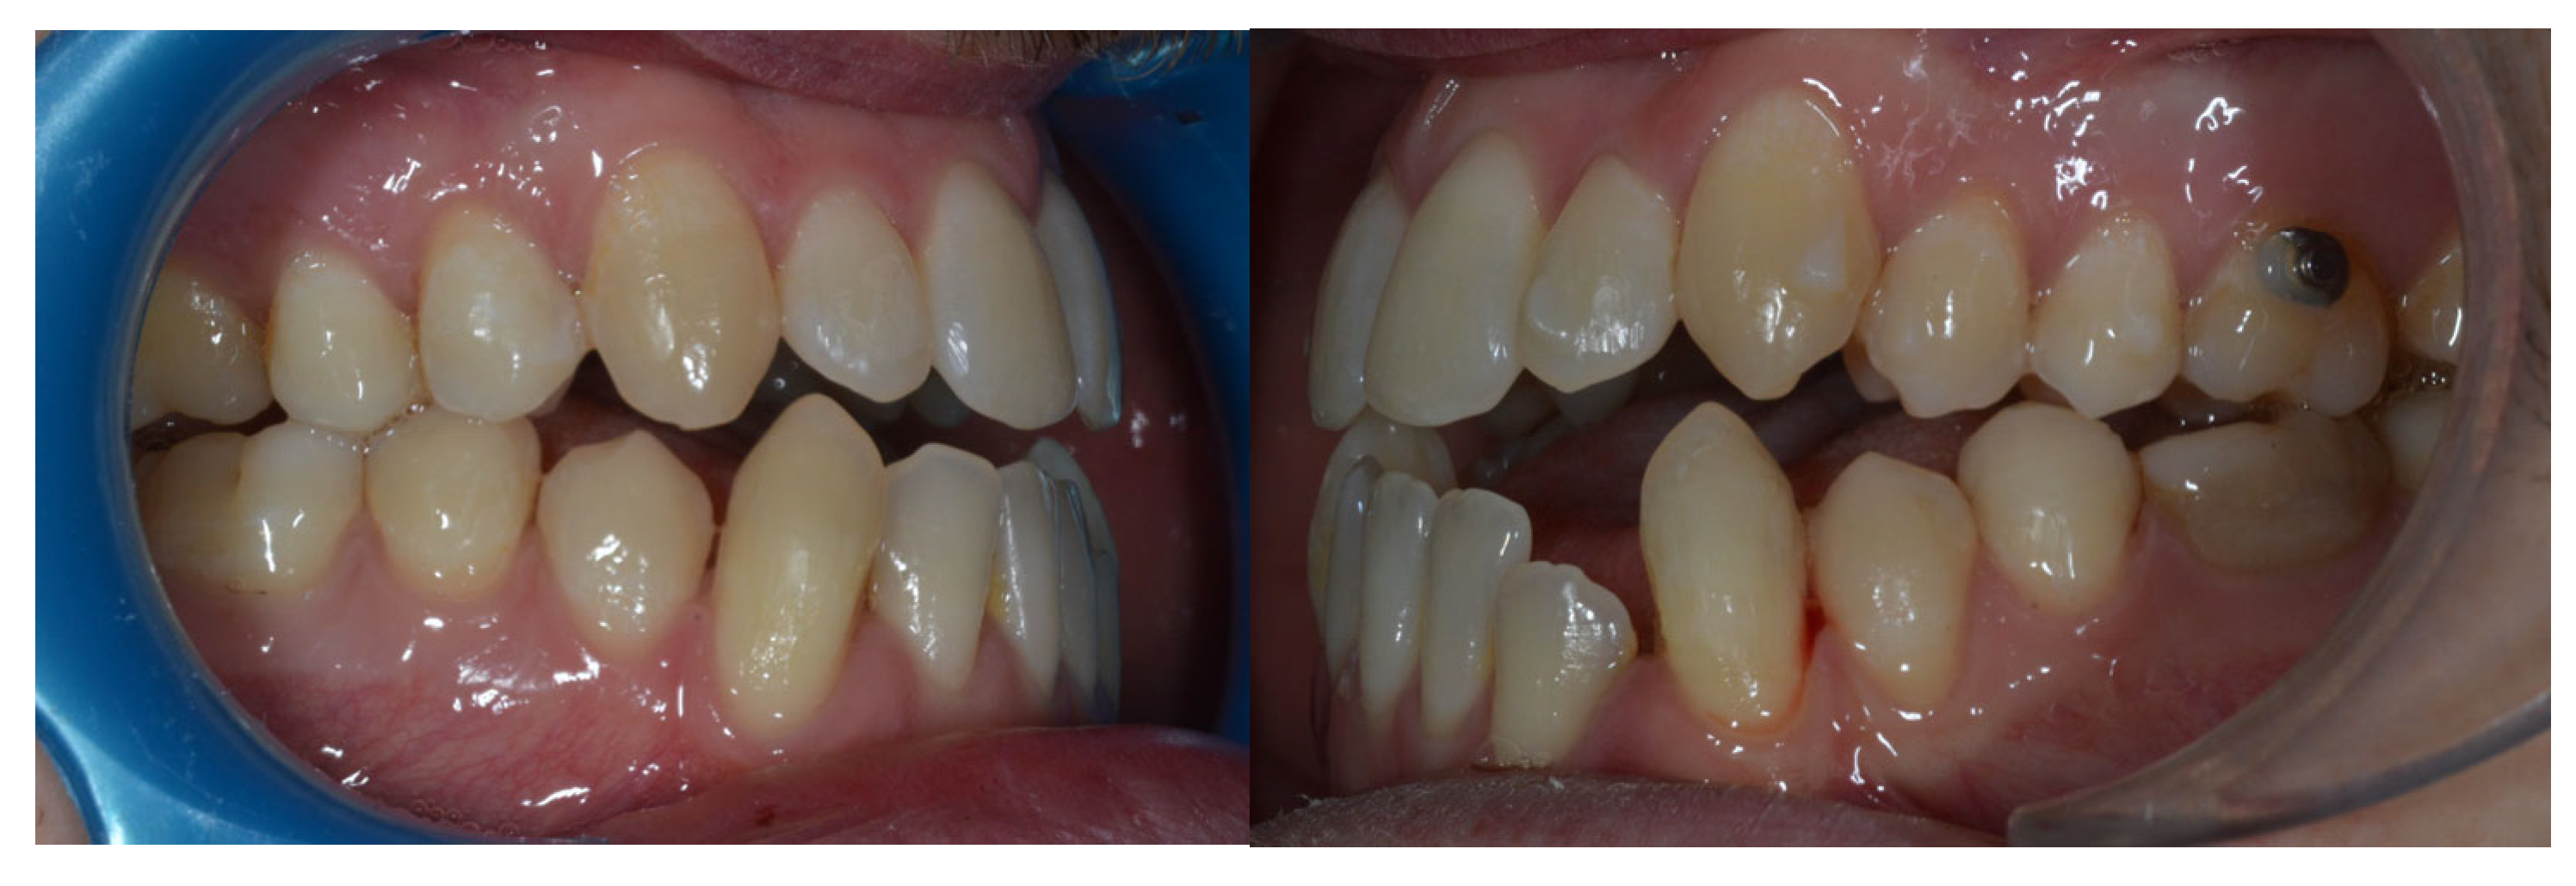

2.4. Treatment Results

A Class I dental relationship for both canines and molars was achieved, with centered maxillary and mandibular midlines. Periodontally, a loss of the interdental papilla between the lower left lateral incisor and the lower left canine was noted. Radiographs were obtained following the loss of the lower left first molar due to pulpitis, which was subsequently replaced with an osseointegrated implant and a ceramic crown (Figure 5).

Figure 5. Final records.

Post-treatment cephalometric analysis revealed an improvement in the skeletal Class III relationship attributed to clockwise mandibular rotation, evidenced by increased vertical divergence (Table 1). This had a positive effect on the sagittal projection of the chin. This is consistent with the mechanism of vertical compensation of a sagittal problem, as seen in the MEAW technique and also with the Class III Carriere® Motion Distalizer as an alternative approach.

Table 1. Changes in the patient’s cephalometric values.

Dentoalveolar changes effectively compensated for the Class III malocclusion, with almost any maxillary incisor protrusion, and significant mandibular incisor extrusion and retroclination, improving interarch relationships. The upper molars showed extrusion in order to compensate for the change in the occlusal plane induced by the use of CLIII elastics. The lower molars showed distal inclination of the crown, consistent with the dental correction of the CLIII relationship. The overjet was corrected from −1.7 mm to 2.7 mm, and the overbite was maintained at 1.7 mm (previously 1.9 mm), ensuring stable occlusal harmony (Table 1, Figure 6).